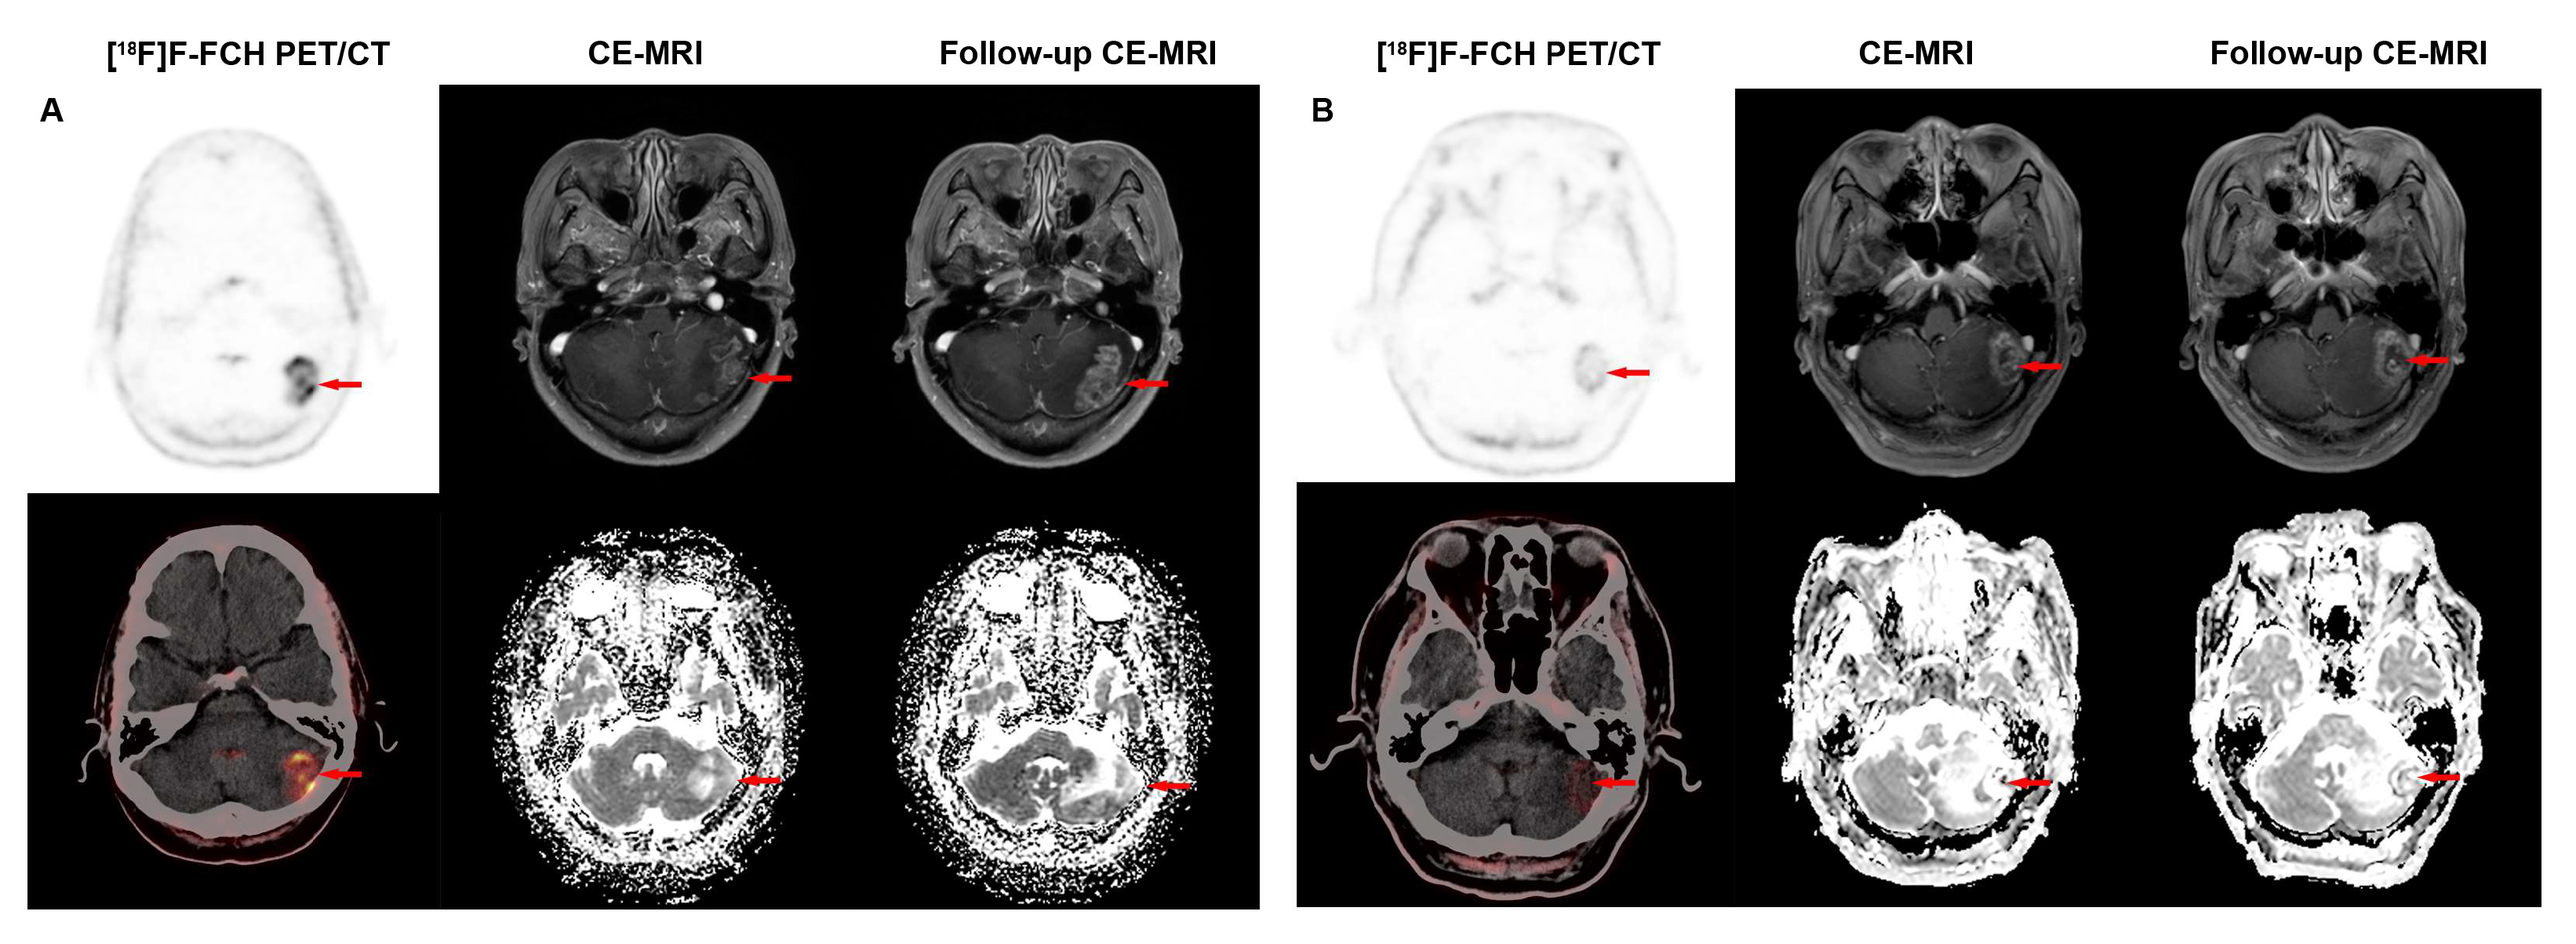

3.2. Diagnostic Performance of [18F]F-FCH PET/CT and CE-MRI in Detecting Recurrence of BM in LCBM After SRS

3.3. Comparison of Diagnostic Performance of [18F]F-FCH PET/CT and CE-MRI in Detecting Lesion Distributions and Sizes of Recurrent BM